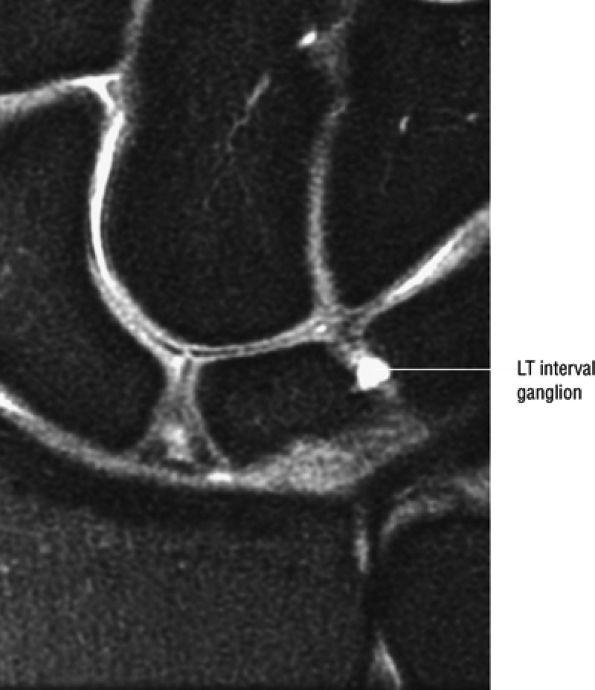

FIGURE 10.35 LUNOTRIQUETRAL LIGAMENT.

|